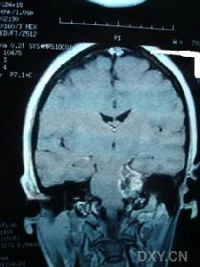

(2)CT及MRI扫描:CT表现为瘤体呈等密度或低密度,少数呈高密度影像。肿瘤多为圆形或不规则形,位于内听道口区,增强效应明显。MRIT1加权像上呈略低或等信号,在T2加权像上呈高信号。第四脑室受压变形,脑干及小脑亦变形移位。注射造影剂后瘤实质部分明显均一强化,囊变区不强化。

(3)CT及MRI检查:目前听神经鞘瘤诊断的标准是Gd-DTDA增强的MRI,特别是当肿瘤很小(<1cm)或在内听道内,CT扫描阴性又高度怀疑肿瘤存在时应该进行GD-DTPA增强的MRI。CT与MRI两种检查有相辅相成的作用,如CT发现有病侧内听道扩大时,增强CT可发现肿瘤对于估计中颅窝入路时颞骨的气化程度及高颈静脉球与后半规管及底的距离有帮助。如果病人已作了CT而肿瘤较大,MRI可提供对脑干压迫的范围Ⅳ脑室是否通畅脑积水、是否存在的情况对可疑听神经鞘瘤或CT检查难于确定时,全序列的MRI可做出鉴别诊断。但也要注意Gd-DTPA的可能假阳性,这与内听道内神经的炎症或蛛网膜炎有关;任何小的接近底部的增强病变应该在六月后作MRI复查,以评估其生长情况。